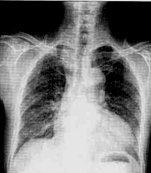

| 病史:男性,65歲,活動(dòng)后胸悶6個(gè)月。既往高血壓病史15年。診斷: |

| ○ 靴型心 | |

| ○ 梨形心 | |

| ○ 普大型心臟 | |

| ○ 正常心臟 | |

| ○ 以上均不是 |